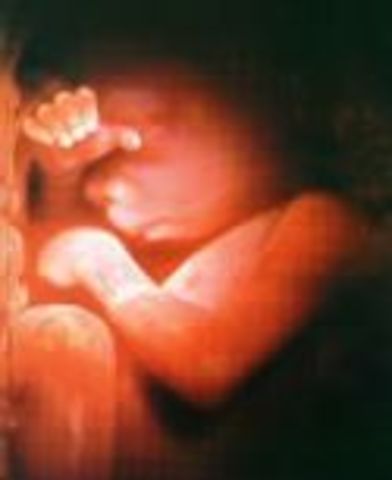

• Week 24: Breathing

Week 24: Breathing

By this week, the baby is 12 inches long and weighs 1.3 pounds. The baby is now practicing how to breathe since branches of the respiratory tree are forming in its lungs. It is currently being covered by hair. The baby is beginning to look like an actual baby with increasing facial features.

Facts: The child is now gaining 3 ounces a week

-36% of babies can survive premature birth at 24 weeks